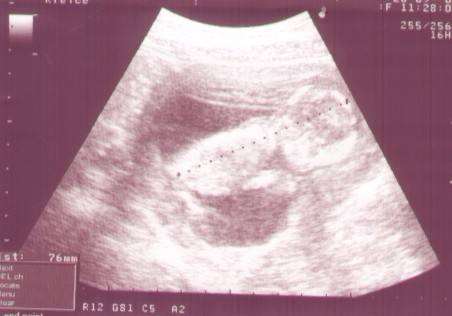

a to moje usg kontrolne, z niedzieli. Skanowane i jakoś słabo przez to wyszło, ale myślę że dzidziusia bedzie widać jak sie powiększy fotkę :-)

Teraz ma 76 mm i jest młodszy z usg o 5 dni niż z OM.

Najbardziej podoba mi się pierwsze, tak fajnie kręgosłupek widać:) duży buziak w brzusio